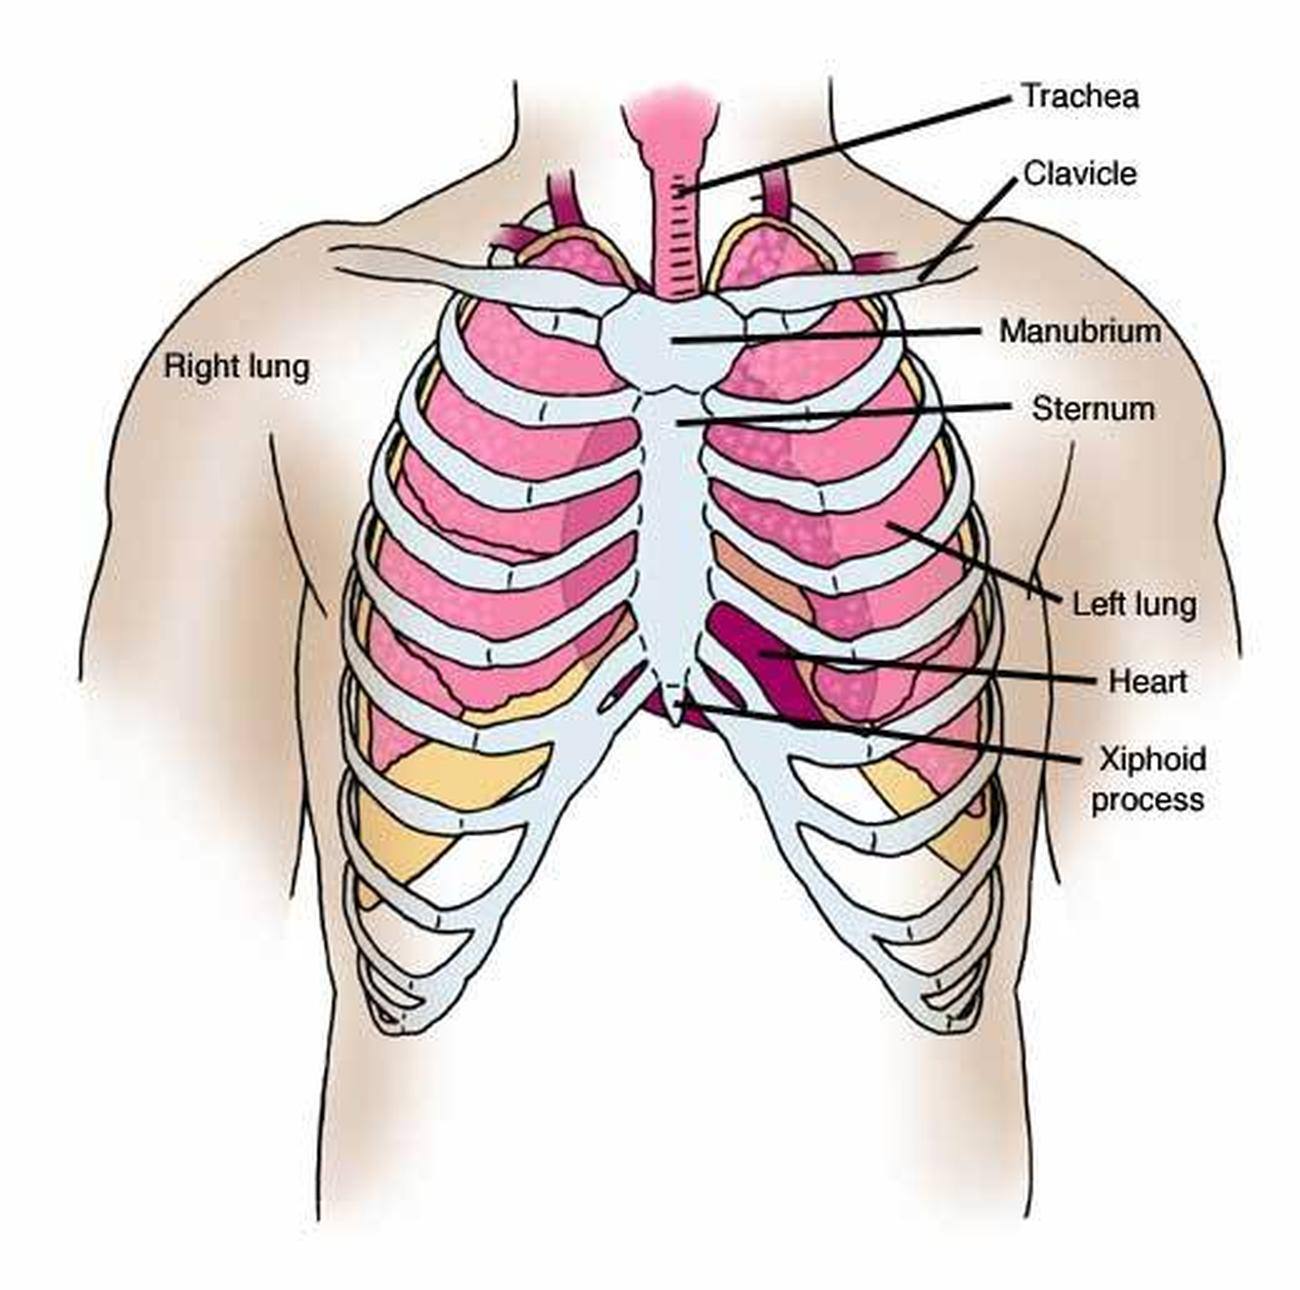

Intro to Anatomy 6: Tissues, Membranes, Organs – Freethought Forum

anatomy of torso organ

Organ Under The Rib Back On The Right Side – Left Abdominal Pain: Lower …

Chest Muscle Anatomy Diagram / 12 photos of the chest muscle anatomy …

Anatomical Positions – SCIENTIST CINDY

Pressure On Chest

Pictures Of Chest